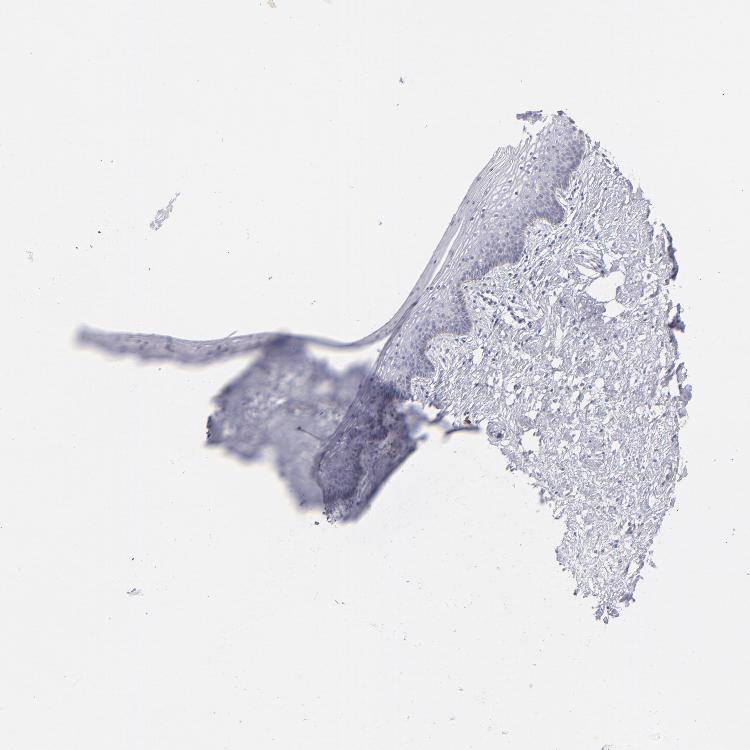

TISSUE PRIMARY DATA VAGINA Show tissue menu

VAGINA - Antibody stainingi

Antibody staining in the annotated cell types in the current human tissue is reported as not detected, low, medium, or high, based on conventional immunohistochemistry profiling in selected tissues. This score is based on the combination of the staining intensity and fraction of stained cells.

Each image is clickable and will lead to virtual microscopy that enables deeper exploration of all samples and also displays staining intensity scores, fraction scores and subcellular localization as well as patient and tissue information for each sample.

Antibody HPA036348Antibody HPA036349Antibody CAB002422Antibody CAB005258

Squamous epithelial cells MediumMediumNot detectedLow